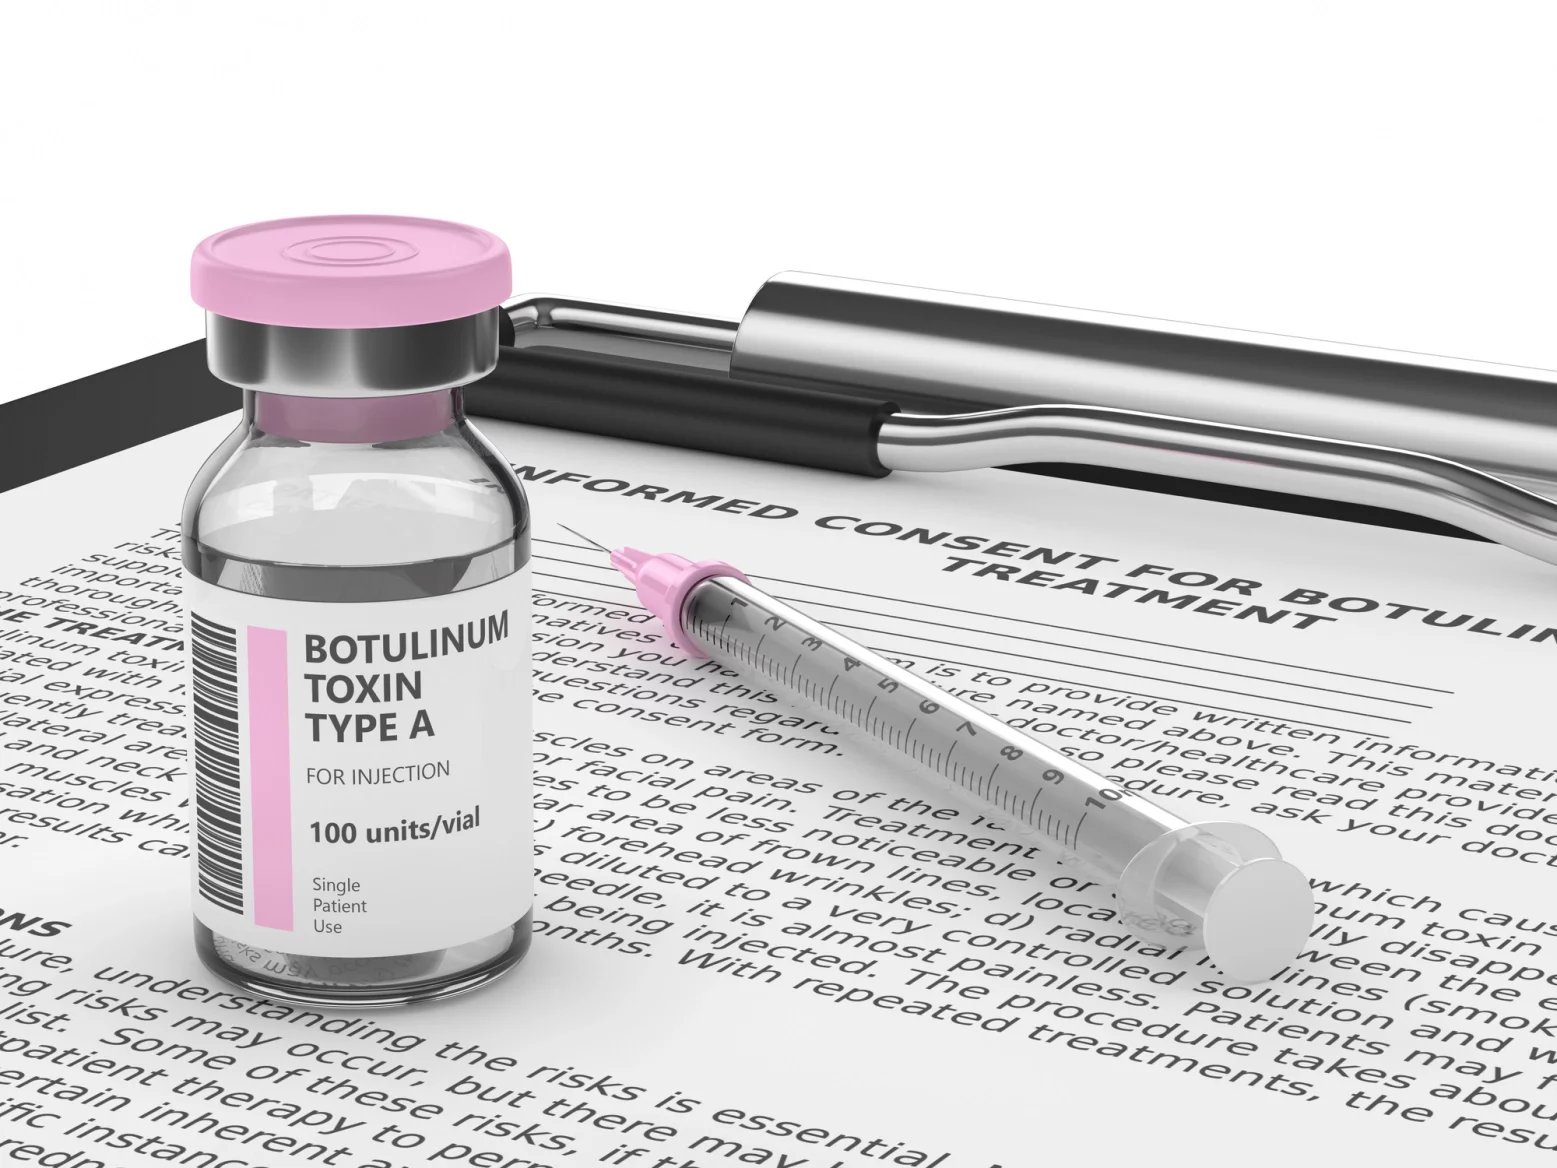

Proč se používá botulotoxin

K úlevě od potíží se používá i botulotoxin. Jeho aplikaci v posledních letech nabízí stále více stomatologických klinik. Ošetření není hrazeno z veřejného pojištění, proto jde plně za klientem. Aplikace do svalů levé i pravé tváře vyjde na několik tisíc korun. Zpravidla 5 až 10 tisíc. Je také potřeba počítat s tím, že účinek je dočasný a případně je nutné aplikaci opakovat.

Výhodou ovšem je, že pokud léčba pacientovi sedne, neřeší jen následky onemocnění, ale samotnou podstatu. Botulotoxin dokáže uvolnit čelistní svaly, u pacientu s bruxismem zvětšené, a snížit frekvenci a intenzitu skřípání zubů,

Aplikujeme jej do velkého žvýkacího svalu, který se nazývá musculus masseter. Tím dojde k dočasnému snížení jeho funkce,

Nepatří do rukou každého

Portál Nzip uvádí, že tato metoda není doporučovaná, protože vede k nekontrolovatelné ztrátě kostní hmoty čelistní kosti, jež je v některých případech neléčitelná. Zubní lékaři s tím ale nesouhlasí. Shodují se ovšem v tom, že není pro každého pacienta s bruxismem a aplikaci botulotoxinu musí předcházet důkladné zvážení indikace.

Je to cesta léčby, v některých zemích EU i hrazená, ale jen v přesně daných případech, nikoliv byznys na kšeft,

Upozorňuje, že lékař, který aplikaci indikuje a provádí, musí být komplexně vzdělaný stomatolog, tedy ideálně stomatochirurg se specializací na léčbu onemocnění čelistního kloubu a souvisejících tkání. Předcházet jí musí také pečlivě provedené neurologické vyšetření.

Aplikace botulotoxinu není vhodná pro všechny pacienty. Je to proto, že skřípání zubů má mnoho příčin a některé lze odstranit neinvazivně. Využíváme v první řadě režimová opatření, fyzioterapii, psychoterapii, noční dlahy a tak dále, ale při výrazném bruxismu můžeme využít právě i aplikaci botulotoxinu do velkého žvýkacího svalu. Jde spíše o jednorázovou pomoc, nemělo by rozhodně jít o jediný způsob terapie,

Stomatolog Petr Chalupa podotýká, že botulotoxin je vhodné využít u pacientů, u nichž jiné metody léčby selhaly. Pomoci může také těm, kteří mají výraznou bolest nebo hypertrofii čelistních svalů.

Naopak kontraindikací je těhotenství, kojení či neuromuskulární poruchy a některá další neurologická onemocnění.

Kam a kolik botulotoxinu se dává

Botulotoxin má podobu tekutiny ve stříkačce s velmi tenkou jehlou. Aplikuje se zpravidla do obou stran obličeje. Symetrie zabraňuje nerovnoměrnému uvolnění svalů.

Po dezinfekci kůže se aplikuje jehličkou přímo do svalu. Na každou stranu tři až pět vpichů,

popisuje parodontoložka Kamila Cmíralová.

Dávka se liší v závislosti na velikosti a síle svalu a míře bruxismu. Obvykle se aplikuje 30 až 40 jednotek na každou stranu, ale přesné množství určí lékař podle individuálních potřeb pacienta,

říká stomatolog Petr Chalupa.

Účinek botulotoxinu nastupuje během sedmi až deseti dnů.

Před zákrokem není nutná žádná speciální příprava. Lékaři ale doporučují se 24 hodin předem vyhnout alkoholu a lékům na ředění krve, tedy třeba i aspirinu. To proto, aby se minimalizovalo riziko, že na obličeji vzniknou modřiny.

Aplikace trvá do deseti minut a není po ní třeba žádná dlouhá rekonvalescence. Pacient může ihned po zákroku odejít domů. Právě rychlost je u této metody výhodou.

Bezprostředně po aplikaci je dobré místo chladit. Čtyři až šest hodin pacient nesmí lehat, předklánět se, dotýkat se a masírovat si ošetřenou oblast. Nejméně jeden den po zákroku by se měl vyhýbat intenzivní fyzické námaze, přímému slunci, saunování, horkým koupelím či návštěvě solária. Dobré je také den nepoužívat v místě ošetření make-up.

Po aplikaci se může objevit zarudnutí a bolestivost v místě vpichu, případně modřinka. Do týdne však tyto příznaky zmizí. Nežádoucím účinkem může být dočasná slabost svalu, pacientům se může hůř žvýkat tvrdší potrava,

upozorňuje Kamila Cmíralová.

Zubní lékaři se shodují, že pokud je podání provedené správně, mimiku obličeje botulotoxin aplikovaný do žvýkacích svalů neovlivňuje a trvale nenarušuje ani funkci čelistí.

Účinek botulotoxinu zpravidla vydrží tři až šest měsíců, pak postupně slábne. Zákrok proto někteří pacienti podstupují opakovaně. Po několika aplikacích to může být ale méně často, protože svaly ztrácí svou sílu,

říká Petr Chalupa.